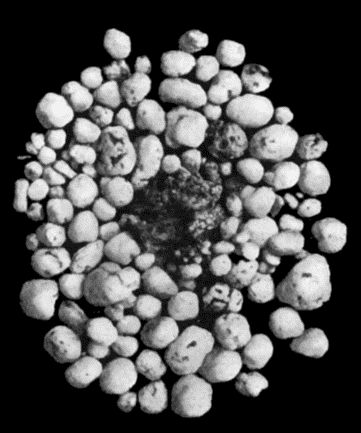

30.Colony of Actinomyces 126

140.Multiple Cartilaginous Exostoses 484

141.Multiple Cartilaginous Exostoses 486